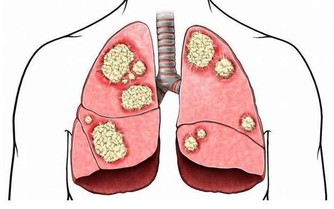

飲用方法: 1.每日約一杯(50毫升),年紀大的人每次20毫升左右; 2.每日飲一至兩次; 3.浸過酒的洋蔥片一起食用更好; 4.不喝酒的人,可用兩倍左右的開水稀釋後飲用或每次倒入電鍋內煮約4至5分鐘,蒸發酒精後飲用。 5.若然喜歡甜的,可加入一點蜂蜜。 紅酒泡洋蔥在日本非常流行!它究竟能治哪些病? 一. 高血壓的患者,飲了之後血壓正常且安定,還能降低糖尿值,降低血糖。 二. 最妙的是對老花眼也有很大的改善,長期飲用後不用戴眼鏡也可以閱讀一般的周刊、雜誌。 三. 每晚都要去幾次廁所的夜晚頻尿症,喝了兩天後,不可思議地恢復正常了。 四. 每天夜裡醒來,一直到天亮都不能再入睡的,或者不吃安眠藥就睡不著的失眠族,飲用後也會逐步緩解失眠症狀。 五. 眼睛疲勞後看東西模糊不清,喝了之後第二天就好多了。 六. 經常肚子會脹,有便秘的人,喝了後第二天便可正常排便。 花錢不多又簡單的方法,功效很顯著,不妨一試哦! 討厭吃洋蔥嗎?看看下面的文章,即使它不那麼可口,為了身體好,也請多多食用! 【洋蔥比骨質酥鬆症的藥有效】 很多人不愛用洋蔥做菜,切的時候會讓人流眼淚,很多人也很討厭洋蔥味。但是想要讓自己骨骼結實、身體長得高、預防骨質酥鬆症的人,最好還是乖乖地捏著鼻子吃洋蔥吧。因為權威期刊「自然」的最新研究報告指出,洋蔥是最能夠防止骨質流失的一種蔬菜。洋蔥預防骨質流失的效果,甚至比骨質酥鬆症治療藥品還要好! 【洋蔥可以預防膽固醇過高】 據哈佛醫學院心臟科教授介紹,每天生吃半個洋蔥,或喝等量的洋蔥汁,平均可增加心臟病人約30%的HDL含量(HDL為高密度脂蛋白膽固醇,一種被認為有助於預防動脈粥狀硬化的膽固醇,也是一種的好的膽固醇)有利於保護心臟。 【洋蔥可以分解脂肪】 克多博士讓診所里的心臟病人每天吃洋蔥,結果發現洋蔥里所含的化合物也能阻止血小板凝結,並加速血液凝塊溶解。所以,當你享用高脂肪食物時,最好能搭配些許洋蔥,將有助於抵銷高脂肪食物引起的血液凝塊。所以說牛排通常搭配洋蔥一起吃,是很有道理的。 【洋蔥可以預防胃癌】 洋蔥和大蒜、大蔥、韭菜這些蔥屬蔬菜,都含有抗癌的化學物質,研究人員在中國山東省一個胃癌罹患率很高的地方所做的調查發現,當洋蔥吃得越多,得胃癌的機率就越低。 【洋蔥可以對抗哮喘】 洋蔥含有至少三種抗發炎的天然化學物質,可以治療哮喘。由於洋蔥可以抑制組織胺的活動,而組織胺正是一種會引起哮喘過敏症狀的化學物質。另外根據德國的研究,洋蔥可以使哮喘的發作機率降低。